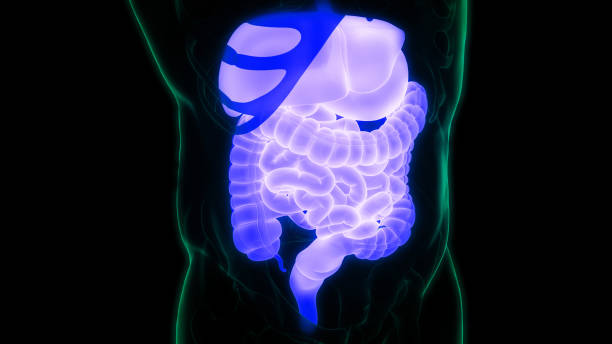

4. 이물질이 섞인 변

마지막으로, 위암 환자들은 종종 변을 보면서 이물질이 섞여 나오는 것을 경험합니다.

이물질이 섞인 변은 피가 섞인 것이 아니라 까맣고 끈적한 변으로 나오기 때문에 주의해야 합니다.

변을 보고 이물질이 섞인 경우, 즉시 병원을 찾아 검진을 받아야 합니다.